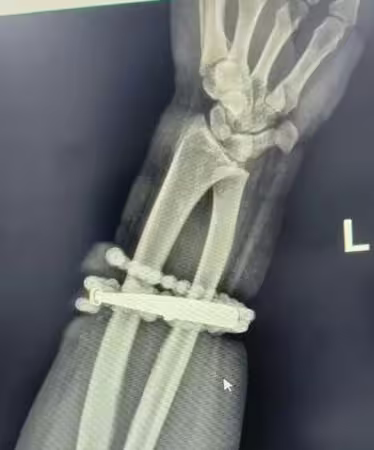

中國福建省寧德市一名33歲的龔姓女子,手腕上佩戴的銀手鐲與串珠,幾乎整整10年從未取下,隨著近年體重增加,手鐲逐漸變緊,她雖感覺勒手,但一直未多加在意。直到最近半年,手腕頻繁出現發癢、發紅,龔女以為只是皮膚炎,便自行買藥膏塗抹,未料狀況惡化,X光照更是駭人。

翻攝自巴士的報,下同

根據《巴士的報》報導,龔女長期佩戴首飾,即便體重增重、手鐲變緊也部願取下,手腕疼痛劇烈、紅腫明顯,兩週前情況更加惡化,甚至有膿液滲出,她仔細查看才驚覺,手鐲與串珠竟已「長進肉裡」,無法自行取下。

龔女急忙就醫,醫師檢查後發現,飾品已深深嵌入皮膚與肉中,導致嚴重感染。

對此,醫師解釋,這是典型的首飾長期壓迫與摩擦,加上細菌感染,造成慢性發炎與肉芽組織增生,手鐲成了刺激與污染的病灶,若再延誤治療,恐引發敗血症或手臂功能受損。

經過一個多小時手術,醫療團隊終於將銀手鐲和串珠,從龔女厚厚的增生組織中完整剝離,並進行清創、引流與抗感染治療,目前她恢復良好,已順利出院。